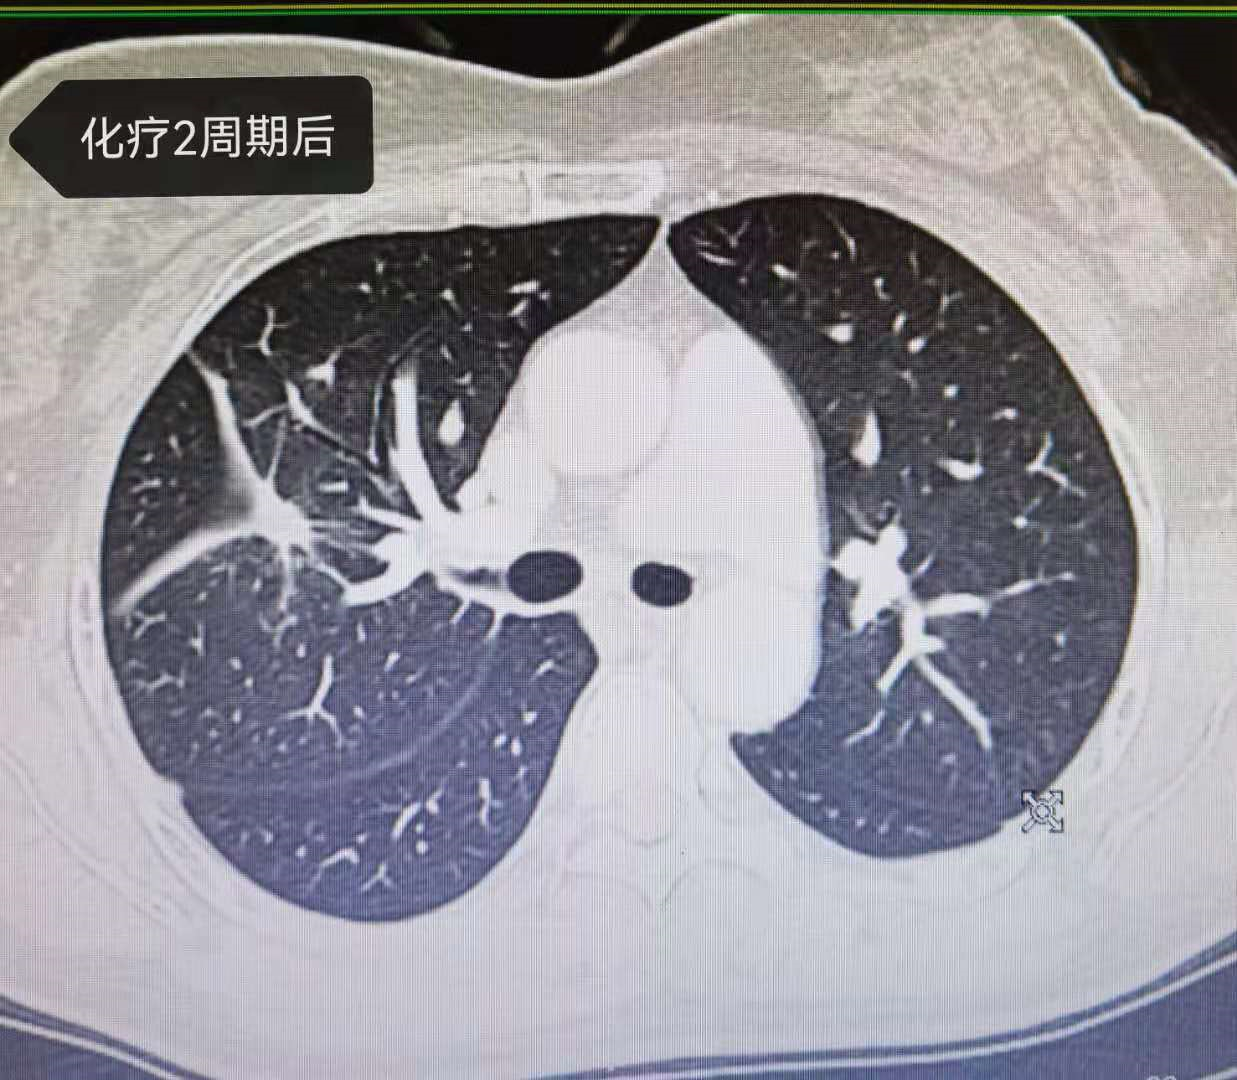

患者确诊后开始口服三代靶向药奥西替尼 , 很可惜 , 5个月就出现耐药 。 建议更换二代靶向药达克替尼 , 但因经济原因 , 未考虑 。 于是 , 选择了医保能报销的较为经济的方案 , 培美曲塞联合卡铂及安维汀 。 经过4周期化疗 , 患者病灶显著缩小 , 疗效显著 。 见图3、4、5、6、7、8